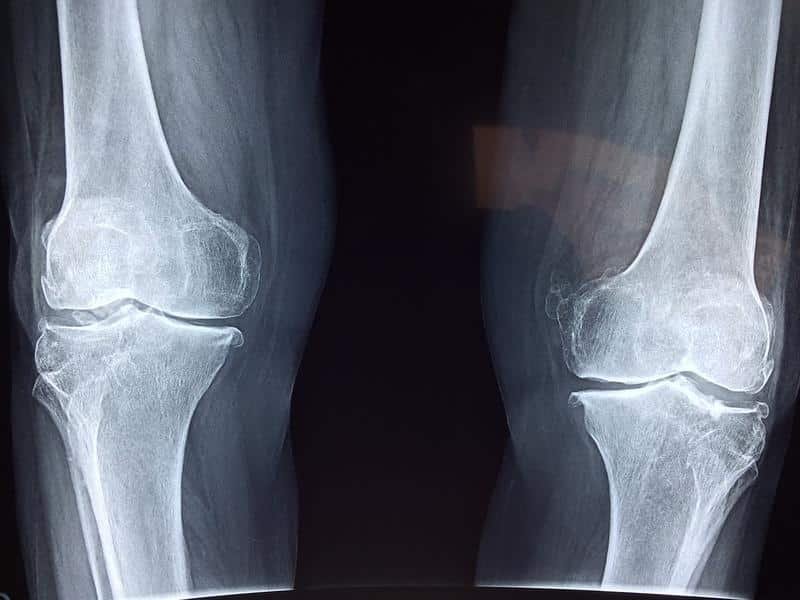

Running injuries are prevalent, especially in the knee and ankle. Many runners experience pain and frustration due to these issues, which often stem from poor biomechanics of running.